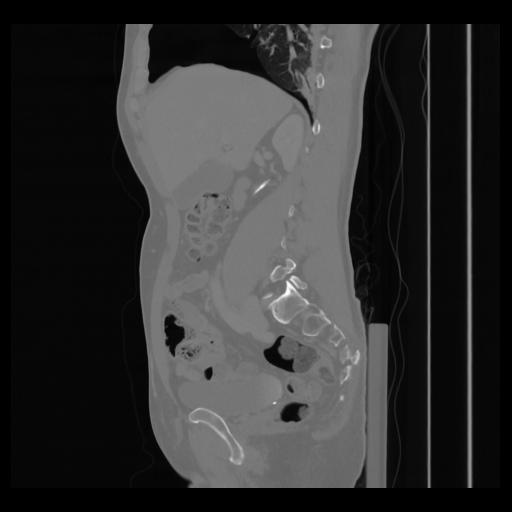

36 CUERPO,CE,Sagittal,3.000,CUERPO,Sagittal,